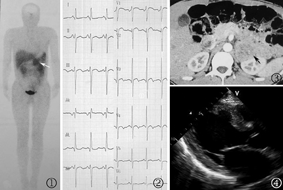

超声检查:双肾正常,左肾上腺实性占位,双肾动脉主干血流速度偏低。生长抑素受体显像未见异常。131I-MIBG(间碘苄胍)显像(图1):左肾上腺区可见一异常放射性摄取增高灶。尿常规阴性;血常规:白细胞6.86×109/L,血红蛋白136 g/L,红细胞压积(Hct)39%,血小板231×109/L;血生化:血糖6.5 mmol/L,肝功能、肌酐、尿素氮、尿酸正常,血钾3.5 mmol/L。24 h尿儿茶酚胺(9 am):去甲肾上腺素29.16 μg(16.69~40.65 μg),肾上腺素3.47 μg(1.74~6.42 μg),多巴胺161.07 μg(120.93~330.59 μg);甲状腺功能:游离三碘甲状腺原氨酸(FT3)3.72 pg/ml,游离甲状腺素(FT4)4.25 ng/dl,促甲状腺激素(TSH)2.938 μIU/ml,血管紧张素Ⅱ(AT-Ⅱ)599.76 pg/ml(25.3~145.3),血浆肾素活性(PRA)>12 ng/ml(0.93~6.5 ng/ml),醛固酮(ALD)35.72 ng/ml(6.5~29.6 ng/ml)。

心电图示广泛导联T波低平或双向(图2)。进一步行CT:左肾上腺可见一大小为42 mm×39 mm类圆形软组织肿块,边缘光滑,增强后可见明显不均匀强化,右肾上腺无异常(图3)。超声心动图:升主动脉39 mm,左心室舒张末内径58 mm,左心室厚13 mm,心肌回声增强,LVEF 37%,室间隔及前壁运动减低(图4)。次日查24 h尿儿茶酚胺(8 am):去甲肾上腺素883.29 μg,肾上腺素3.21 μg,多巴胺658.29 μg,N末端脑钠肽前体2596 pg/ml(0~125 pg/ml),肌钙蛋白I 0.17 μg/L。眼底检查:双眼视乳头水肿。给予酚苄明、乌拉地尔、依那普利、卡维地洛、氢氯噻嗪及地高辛治疗。